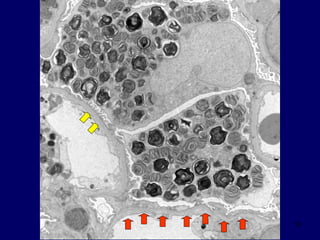

Distal Tubules

20

21

Tubule

Distal Tubule

PTC - Endo

TBM

22